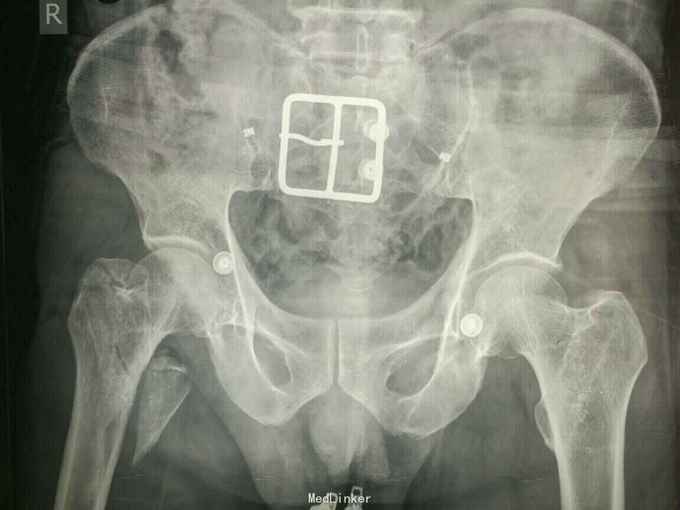

主诉:外伤后右大腿及右髋部疼痛,活动受限2小时 病史:患者自述于2小时前从高处摔伤右下肢及右手,伤后感右髋部右下肢及右手疼痛,活动受限,不能站起行走。自述未伤及头部。由家人送往我院诊治,经详细查体后以“右股骨骨折,右粗隆间骨折,右舟骨骨折”收入院。患者自入院以来精神状态尚可,未进食水,未排二便。

查体:右大腿皮肤无破损,大腿上段及右髋部软组织肿胀,未见皮下淤斑,右髋部及股骨近端环形压痛,局部可触及骨擦感及异常活动,右下肢纵向叩击痛阳性,肢端感觉良好,足背动脉可触及。右手近腕关节处肿胀,舟骨处压痛阳性,叩击痛阳性,右腕关节活动受限。 辅助检查:右髋及大腿x线示右股骨转子间粉碎骨折,对位对线尚可,右股骨干粉碎骨折,对位对线差,右手dr片右舟骨骨折,位置良好。

诊断:右股骨转子间骨折 右股骨干骨折 治疗:切开复位髓内钉固定术